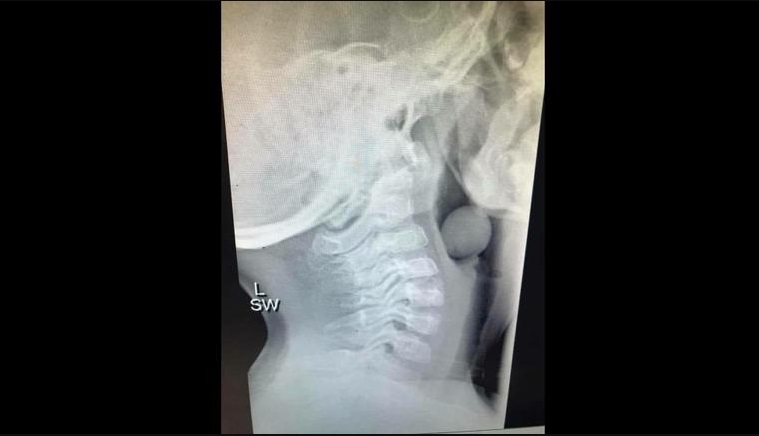

Mama copilului a acceptat să dea publicității radiografia copilului, în care se vede bobița de strugure blocată în gât.

Băiețelul în vârstă de numai cinci anișori a avut nevoie de operație cu anestezie totală pentru a i se extrage boaba de strugure rămasă blocată în gât.